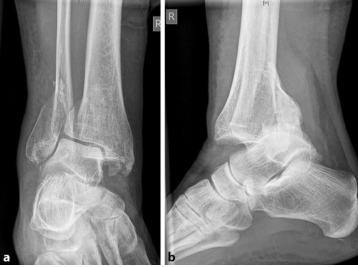

Предварительный диагноз требует большего, чем просто результаты исследования скелета. Необходимо обратить внимание на наличие сопутствующих заболеваний, таких как сахарный диабет, заболевания периферических сосудов, остеопороз, неврологический дефицит, длительный прием лекарств (антикоагулянты, кортикостероиды) и уровень активности до травмы, поскольку эти параметры имеют решающее влияние. о выздоровлении пациента. Визуализирующие исследования. Поскольку у пожилых пациентов часто обнаруживаются сложные модели переломов, рекомендуются дополнительные КТ-исследования. У пожилых пациентов сложные переломы лодыжки, подобные этому (рис. ниже), случаются в одном из четырех случаев. Окклюзионное заболевание периферических артерий обычно проявляется в пожилом возрасте, и адекватная перфузия нижних конечностей является предпосылкой для заживления ран и костей.